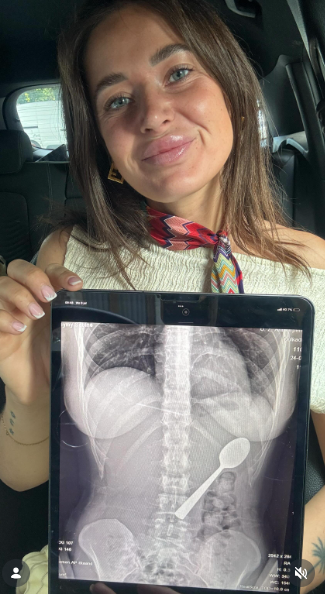

Βέλγιο: 28χρονη κατάπιε κουτάλι 17 εκατοστών όταν πήδηξε πάνω της ο σκύλος της (Βίντεο)

Τον τρόμο βίωσε μια 28χρονη γυναίκα στο Βέλγιο όταν κατάπιε κατά λάθος ένα κουτάλι μήκους 17 εκατοστών ενώ έτρωγε γιαούρτι στο σπίτι της.

Η Reymy Amelinckx, από το Rumst του Βελγίου, είπε ότι το αλλόκοτο περιστατικό συνέβη όταν ο σκύλος της, ο Marley, πήδηξε ξαφνικά πάνω της ενώ καθόταν στον καναπέ.

Με το κουτάλι στο στόμα της και τα χέρια της απασχολημένα, ξαφνιάστηκε από την κίνηση του σκύλου και έχασε τον έλεγχο. «Έβαλα το κουτάλι στο στόμα μου για να έχω τα χέρια μου ελεύθερα για να απαντήσω σε ένα μήνυμα. Ακριβώς τότε, η Μάρλεϊ αποφάσισε να πηδήξει πάνω μου», θυμήθηκε.

«Τρομοκρατήθηκα τόσο πολύ που τράβηξα το κεφάλι μου πίσω και, πριν το καταλάβω, το κουτάλι σφηνώθηκε στο λαιμό μου. Σηκώθηκα και άρχισα να πανικοβάλλομαι».

Μη μπορώντας να βγάλει το κουτάλι, η Reymy Amelinckx είπε ότι αναγκάστηκε να πάρει μια απόφαση σε κλάσματα δευτερολέπτου. Τελικά το κατάπιε, και αργότερα παραδέχτηκε ότι ένιωσε πολύ ντροπή για να το πει αμέσως στον φίλο της όταν επέστρεψε σπίτι. Αρχικά προσπάθησε να αγνοήσει την κατάσταση, πιστεύοντας ότι δεν ήταν σοβαρή.

«Δεν ένιωσα καθόλου άσχημα – οπότε δεν είπα τίποτα γι’ αυτό αμέσως. Μόνο μετά το δείπνο συνειδητοποίησα ότι ήταν στην πραγματικότητα αρκετά σοβαρό. Υπήρχε ένα κουτάλι 17 εκατοστών στο στομάχι μου. Στο διαδίκτυο, παντού έλεγαν το ίδιο πράγμα: πήγαινε κατευθείαν στα επείγοντα. Μόνο τότε συνειδητοποίησα πόσο επικίνδυνο θα μπορούσε να είναι.»

Οι γιατροί αργότερα επιβεβαίωσαν ότι το κουτάλι ήταν πολύ μεγάλο για να περάσει φυσικά και προγραμματίστηκαν γαστροσκόπηση για να το αφαιρέσουν. Η Reymy Amelinckx περιέγραψε την αναμονή για τη διαδικασία ως οδυνηρή.

«Εκείνη η νύχτα ήταν δύσκολη, ένιωθα το κουτάλι να κινείται, μερικές φορές ακόμη και ανάμεσα στα πλευρά μου. Ήταν πραγματικά τρομακτικό.

Ένιωθα φούσκωμα και ναυτία, και δεν μπορούσα να φάω χωρίς να νιώθω περίεργα. Ο ύπνος ήταν δύσκολος επειδή κάθε στάση μου θύμιζε το κουτάλι στο στομάχι μου».

Δύο ημέρες αργότερα, το κουτάλι αφαιρέθηκε με επιτυχία με τοπική αναισθησία, αν και η διαδικασία προκάλεσε μικρή εσωτερική αιμορραγία.